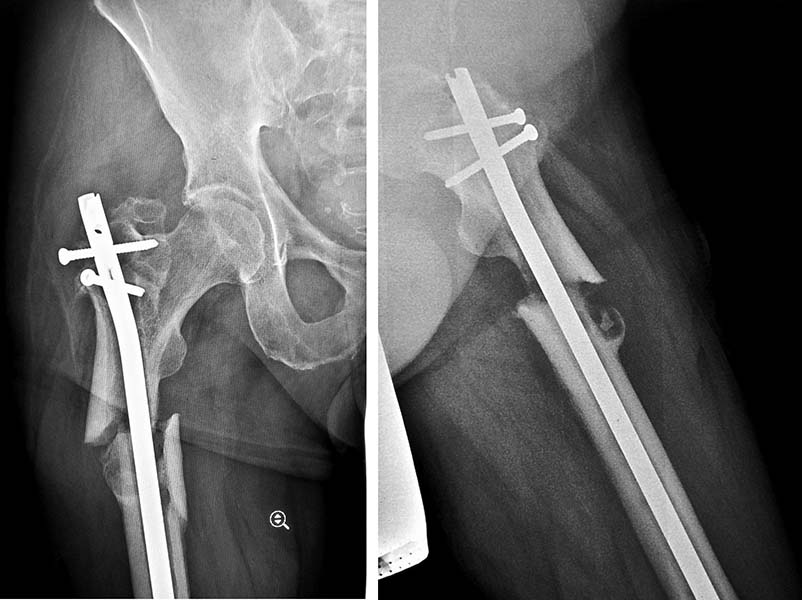

Уважаемые коллеги! Хотелось бы узнать Ваше мнение. Обратился наш с вами

коллега. Травма получена примерно 10 месяцев назад, экстренно оперирован

в городской клинике. Теперь результат. Ходит с костылями из-за болевого

синдрома. Функция соответственно страдает.

Какую ревизионную тактику выбрать? Реконструктивный гвоздь (сам к этому

склоняюсь) или накостный синтез?Спасибо! И с наступающими!)